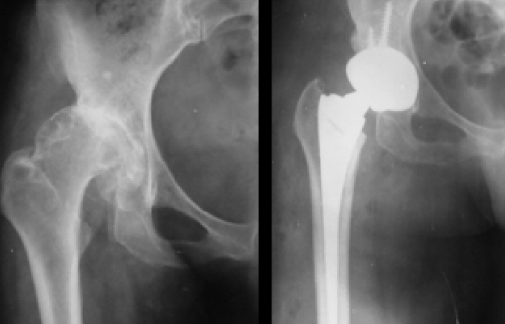

3)الورك المصاب بهذه المشكلة، والذي لم يتم علاجه هو عرضة للإحتكاك والتآكل في سن مبكرة، مما قد يضيف معاناة الألم التي تتزايد مع مرور الوقت والتي تحد بشكل كبير من نشاط الشخص المصاب. هذا الاحتكاك قد يبدأ في سن المراهقة او العشرينيات...

وعند حدوث الاحتكاك في المفصل المصاب بالخلع الولادي لا يمكن علاجه الا بإجراء عمليات استبدال المفصل الطبيعي بمفصل صناعي وهي عملية معقدة وتحد نسبيا من النشاط البدني العالي لمن يتم إجراؤها له .

الخيار الثالث والأخير لعلاج الخلوع الولادية هو عملية الرد المفتوح للخلع الولادي لمفصل الورك مع إصلاح لغطاء المفصل.

العملية مكونة من جزئين رئيسيين:

١- الرد المفتوح: يفتح المفصل المخلوع جراحيا وتتم إزالة جميع العوائق التي تقف فيه طريقه كي يعود إلى تجويفه الطبيعي

٢- إصلاح غطاء المفصل: إصلاح وترميم غطاء المفصل الناقص التكوين وذلك كي يكتسب المفصل الثبات اللازم وتقل نسب الاحتكاك مستقبلا